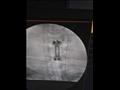

وقال الدكتور سعيد السقعان، وكيل وزارة الصحة بالإسكندرية، إن مستشفى برج العرب المركزي استقبل رجلا يبلغ من العمر 40 عاما من محافظة الشرقية، كان تعرض للسقوط على رأسه أثناء السباحة ما تسبب في إصابته بكسر متفتت في الفقرة العنقية الخامسة.

وأضاف في تصريح صحفي، اليوم الجمعة، أن فريقا جراحي أجرى المصاب جراحة طارئة لاستئصال الفقرة المفتتة ووضع دعامة عنقية وتثبيتها بواسطة شريحة ومسامير وتوسيع القناة العصبية، مبينا أن الجراحة تعد من العمليات الرائدة في مجال جراحات العمود الفقري بالإسكندرية.

أجرى الجراحة فريق طبي برئاسة الدكتور أحمد الرحماني، أخصائي جراحة المخ والأعصاب والعمود الفقري بالمستشفى ، بمعاونة أخصائيي التمريض والأشعة هدى فتوح ومينا عاطف.